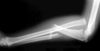

Monteggia injury

(fracture of the ulnar shaft and dislocation of the radial head at the elbow)

With isolated ulnar fractures it is advisable to take an X-ray of the _________

With isolated ulnar fractures it is advisable to take an X-ray of the elbow

(to check for Monteggia fracture)

How are Monteggia fractures treated?

ORIF

(in adults and children)

A _________ fracture involves fracture of the ulnar shaft and dislocation of the proximal radial head at the elbow, whilst a __________ fracture involves a fracture of the radial shaft alongside dislocation of the ulna at the distal radio-ulnar joint

A Monteggia fracture involves fracture of the ulnar shaft and dislocation of the proximal radial head at the elbow, whilst a Galeazzi fracture involves a fracture of the radial shaft alongside dislocation of the ulna at the distal radio-ulnar join